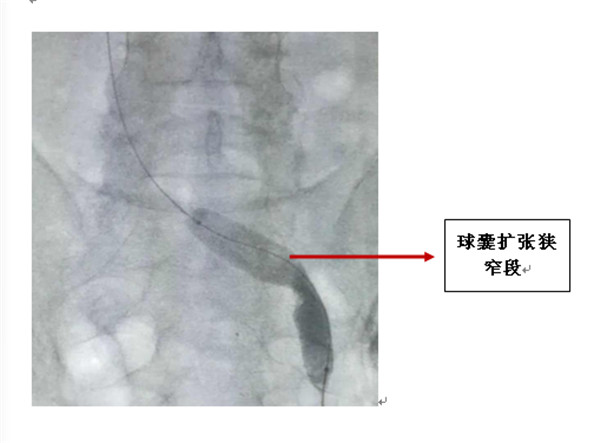

下肢深静脉血栓形成(deep venous thrombosis,DVT)是血管外科常见疾病,发病趋势逐年上升,血栓脱落可能导致肺栓塞,严重者危及生命,特别是右下肢血栓,脱落风险较大。多发于下肢及盆腔深静脉,而对于急性血栓患者如果不能及时有效地消除血栓,解除流出道梗阻或者狭窄,可出现常见的深静脉血栓形成后遗症(postthromboticsyndrome,PTS),据最新统计显示,其发生率约为20%~40%,重症PTS 约为5%~10%,严重影响患者的生活质量;而肺栓塞(pulmonaryembolism,PE)是其最危险的并发症,可致患者突然死亡。DVT成因之一是Cockett 综合征,即左髂总静脉受右髂总动脉压迫致管腔狭窄,引起下肢及盆腔静脉回流受阻,左髂总静脉处于受压位置还不能构成Cockett征发生的原因,只有使静脉受到挤压损伤和前后壁粘连纤维性索条形成,从而导致管腔狭窄或阻塞后,才是Cockett征发生的关键,而合并Cockett 综合征的DVT 患者若不解除狭窄病因,很易复发。据报道左髂总静脉狭窄至正常髂总静脉直径约48%或以上,DVT 发生概率明显增加。Cockett 综合征合并急性DVT 由于存在髂静脉受压或梗阻,单纯溶栓、抗凝治疗临床效果可能欠佳,随着介入技术发展,DVT 治疗发生很大变化,认为综合介入治疗应该作为治疗DVT 首选。近年来,深静脉置管溶栓的应用越来越多,并取得良好疗效,经深静脉置管溶栓+ 球囊扩张,支架植入,疗效较好。

我科借鉴国内外知名血管外科中心,治疗静脉血栓性疾病的经验,开展了静脉血栓性疾病的一站式微创治疗理念。让病人在住院治疗期间,全程微创化解决静脉血栓的疾病痛苦,不再经受疾病反复发作加重、到处寻医问药的折磨。我科采用分阶段、多步骤、程序化的分期手术策略来治疗静脉血栓性疾病。患者入院后完善相关检查,确诊下腔静脉或髂股静脉内有附着很差的可漂移血栓患者,予以植入下腔静脉滤器,导管接触性溶栓,经过3-5天,导管接触性溶栓后,拔除溶栓导管,根据医嘱口服溶栓药物继续治疗,期间密切监测实验室指标变化。一段时间治疗后,溶栓取得明显效果,可根据情况取出下腔静脉滤器,对合并Cockett综合征的患者,进一步予以球囊扩张狭窄段,支架植入,为患者一站式完成治疗,解决患者痛苦。根据不同的分期又采取不同的微创治疗策略。虽然看似病人要经受一个漫长的治疗过程,实际上全程均为高度微创化手术,局部麻醉下操作,减少了手术创伤,加快恢复速度。全部治疗完成后病人在大腿根部仅有针眼大小手术疤痕。而研究显示:这种治疗方式的治疗效果要远远优于传统抗凝、溶栓治疗,而且并发症的发生率显著降低。